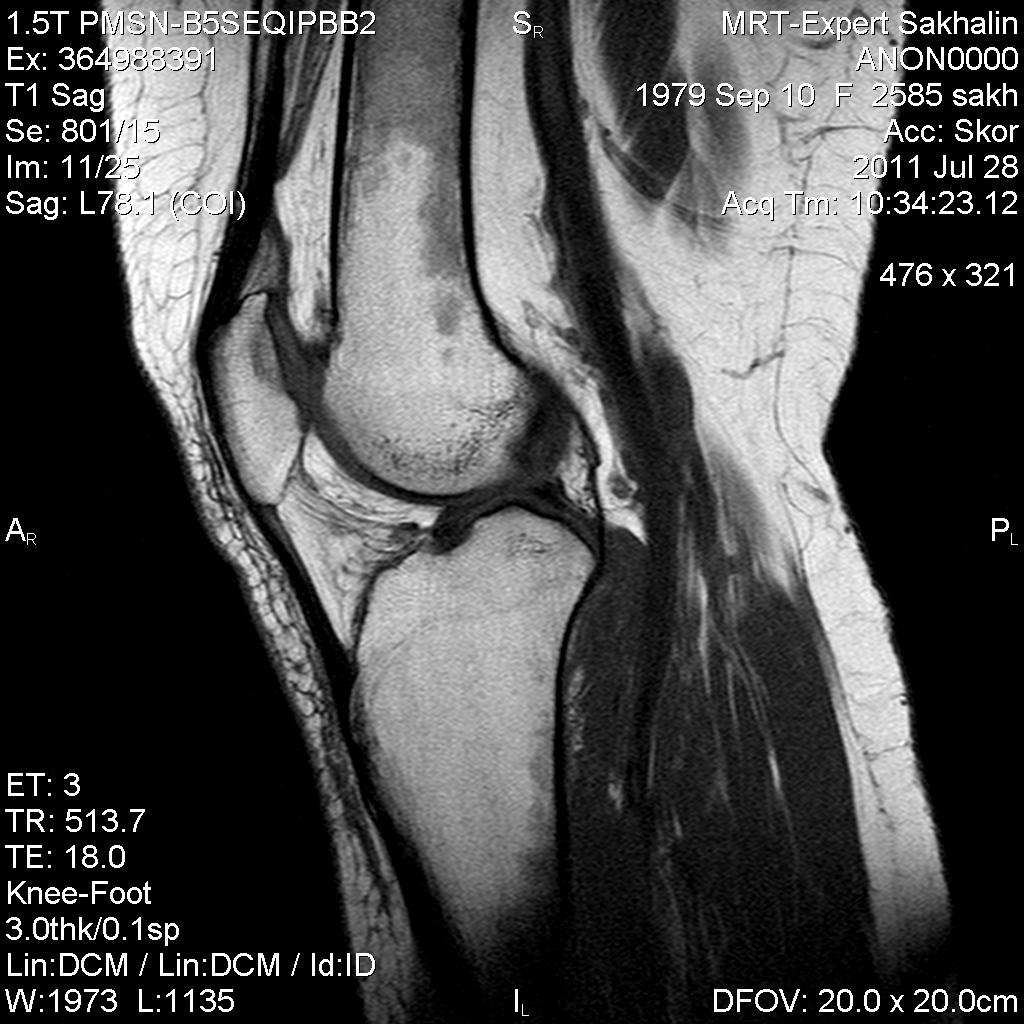

Коленный сустав

Подглядела случай у коллеги.

Что это может быть?

Не вижу криминала. А на что жалуется девушка?

P.S. В костях - это, скорее всего, резидуальный красный костный мозг.

Жалоба у всех одна на всех-болит.

участки гемопоэтического костного мозга